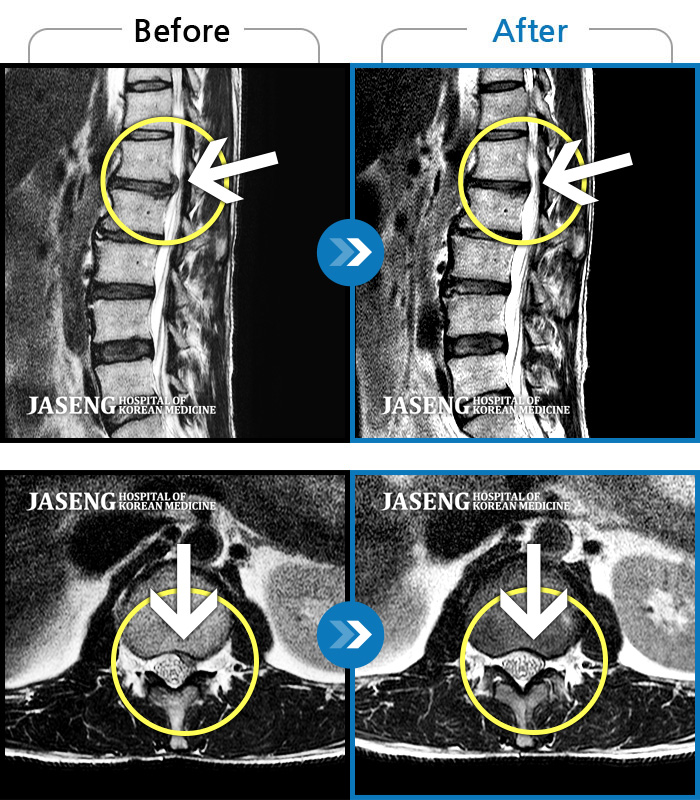

처음 내원시 허리 통증이 심하여 일상생활에 불편감이 있으신 환자분이셨습니다.